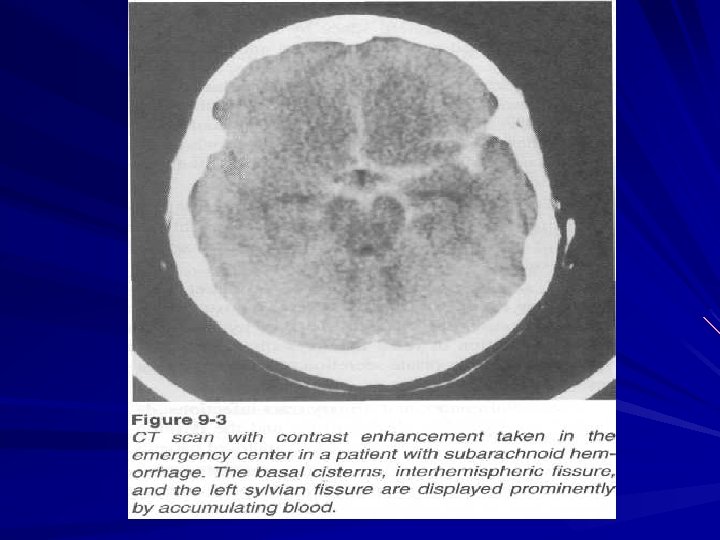

Subarachnoid hemorrhig

Diagnosis Stroke – like development with general cerebral and meningeal symptoms and absence of significant focal neurologic deficit The presence of blood in liquor (bleeding liquor during first day and yellow liquor on 3 rd – 5 th day) Retinal hemorrhages are on eye fundus